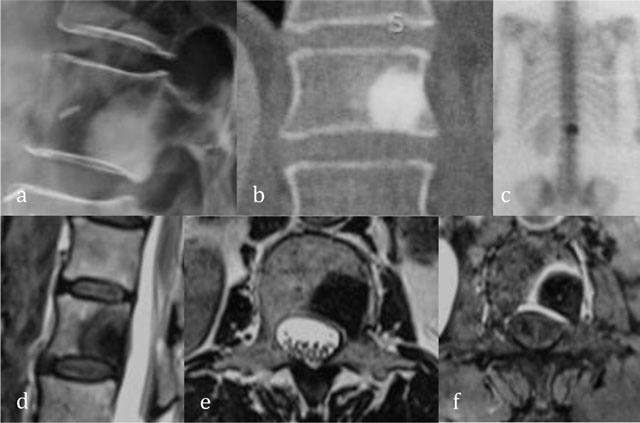

Figure 10

Enostosis of L1. Radiograph (a) and coronal reformatted CT (b) show a focal area of dense bone similar to cortical bone. Bone scintigraphy (c) show an avid uptake. Sagittal T2-WI (d), axial T2-WI (e) and axial T1-WI after administration of gadolinium contrast (f) show central low signal intensity surrounded by intermediate T2 signal and peripheral enhancement.